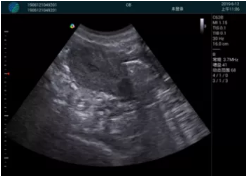

病例一:

清晰顯示孕囊,通過軟件包計算孕齡7w+6d

M20實時引導,術中清晰顯示孕囊被破壞和抽吸針的過程,清晰顯示吸引針

抽吸結束后縱切子宮,孕囊已被完全抽吸,未見明顯殘留

橫切子宮,發(fā)現右側宮腔靠近宮角處有少許脫模樣殘留

M20引導下,抽吸針找到右側宮角處再次清掃

二次抽吸后再次進行超聲檢查,宮腔未見殘留,宮腔線清晰顯示